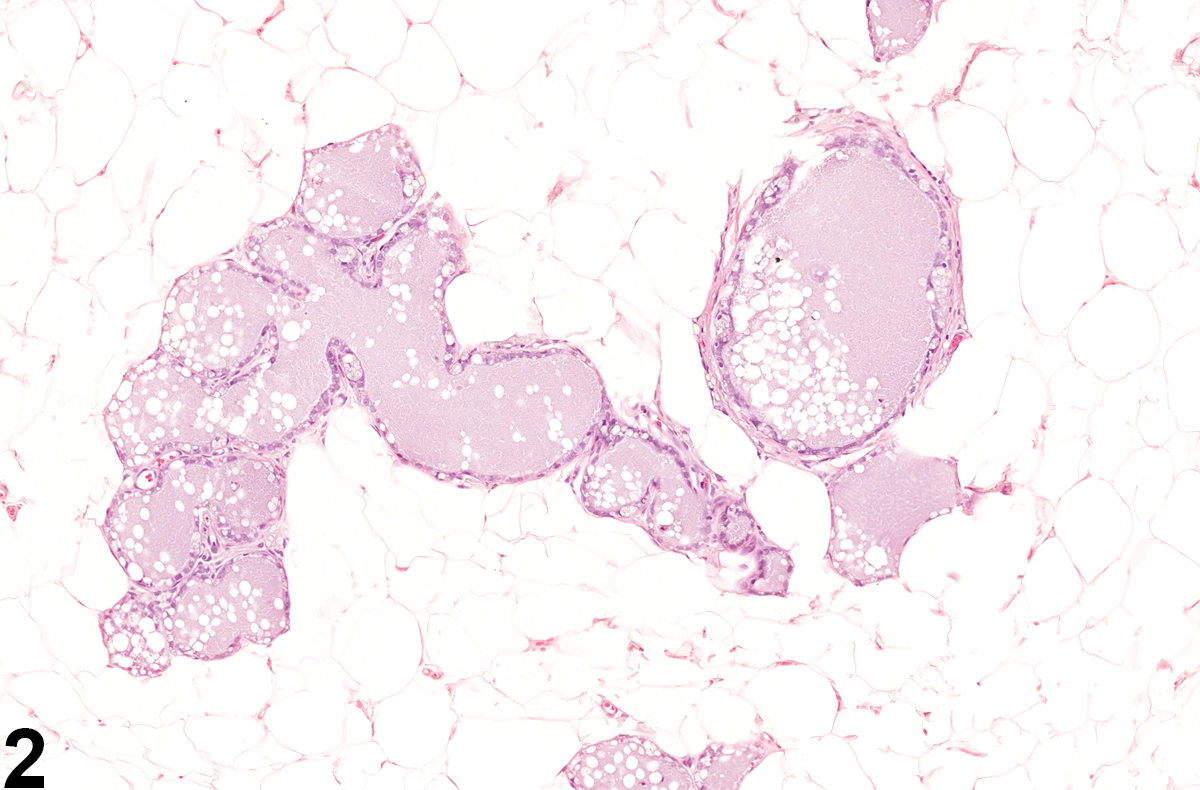

Mammary gland dilation can affect ducts, alveoli, or both. It is often a diffuse change characterized by distention of collecting (lactiferous) ducts and alveoli beneath a nipple by intraluminal accumulations of amorphous, proteinaceous eosinophilic, secretory material, lipid, cell debris, and, sometimes, inflammatory cells. The lining epithelial cells of duct dilation are often vacuolated and can occur with or without epithelial hypertrophy or hyperplasia. Galactoceles are considered an extreme form of dilation and are characterized by focally dilated mammary gland ducts and alveoli that have become cystic and very large, lined by flattened epithelium, and filled with proteinaceous secretory fluid. Galactoceles may rupture and be associated with inflammation and fibrosis.

Mammary gland - Dilation in a female F344/N rat from a chronic study. There are scattered ducts and alveoli distended by intraluminal accumulations of amorphous, secretory material.